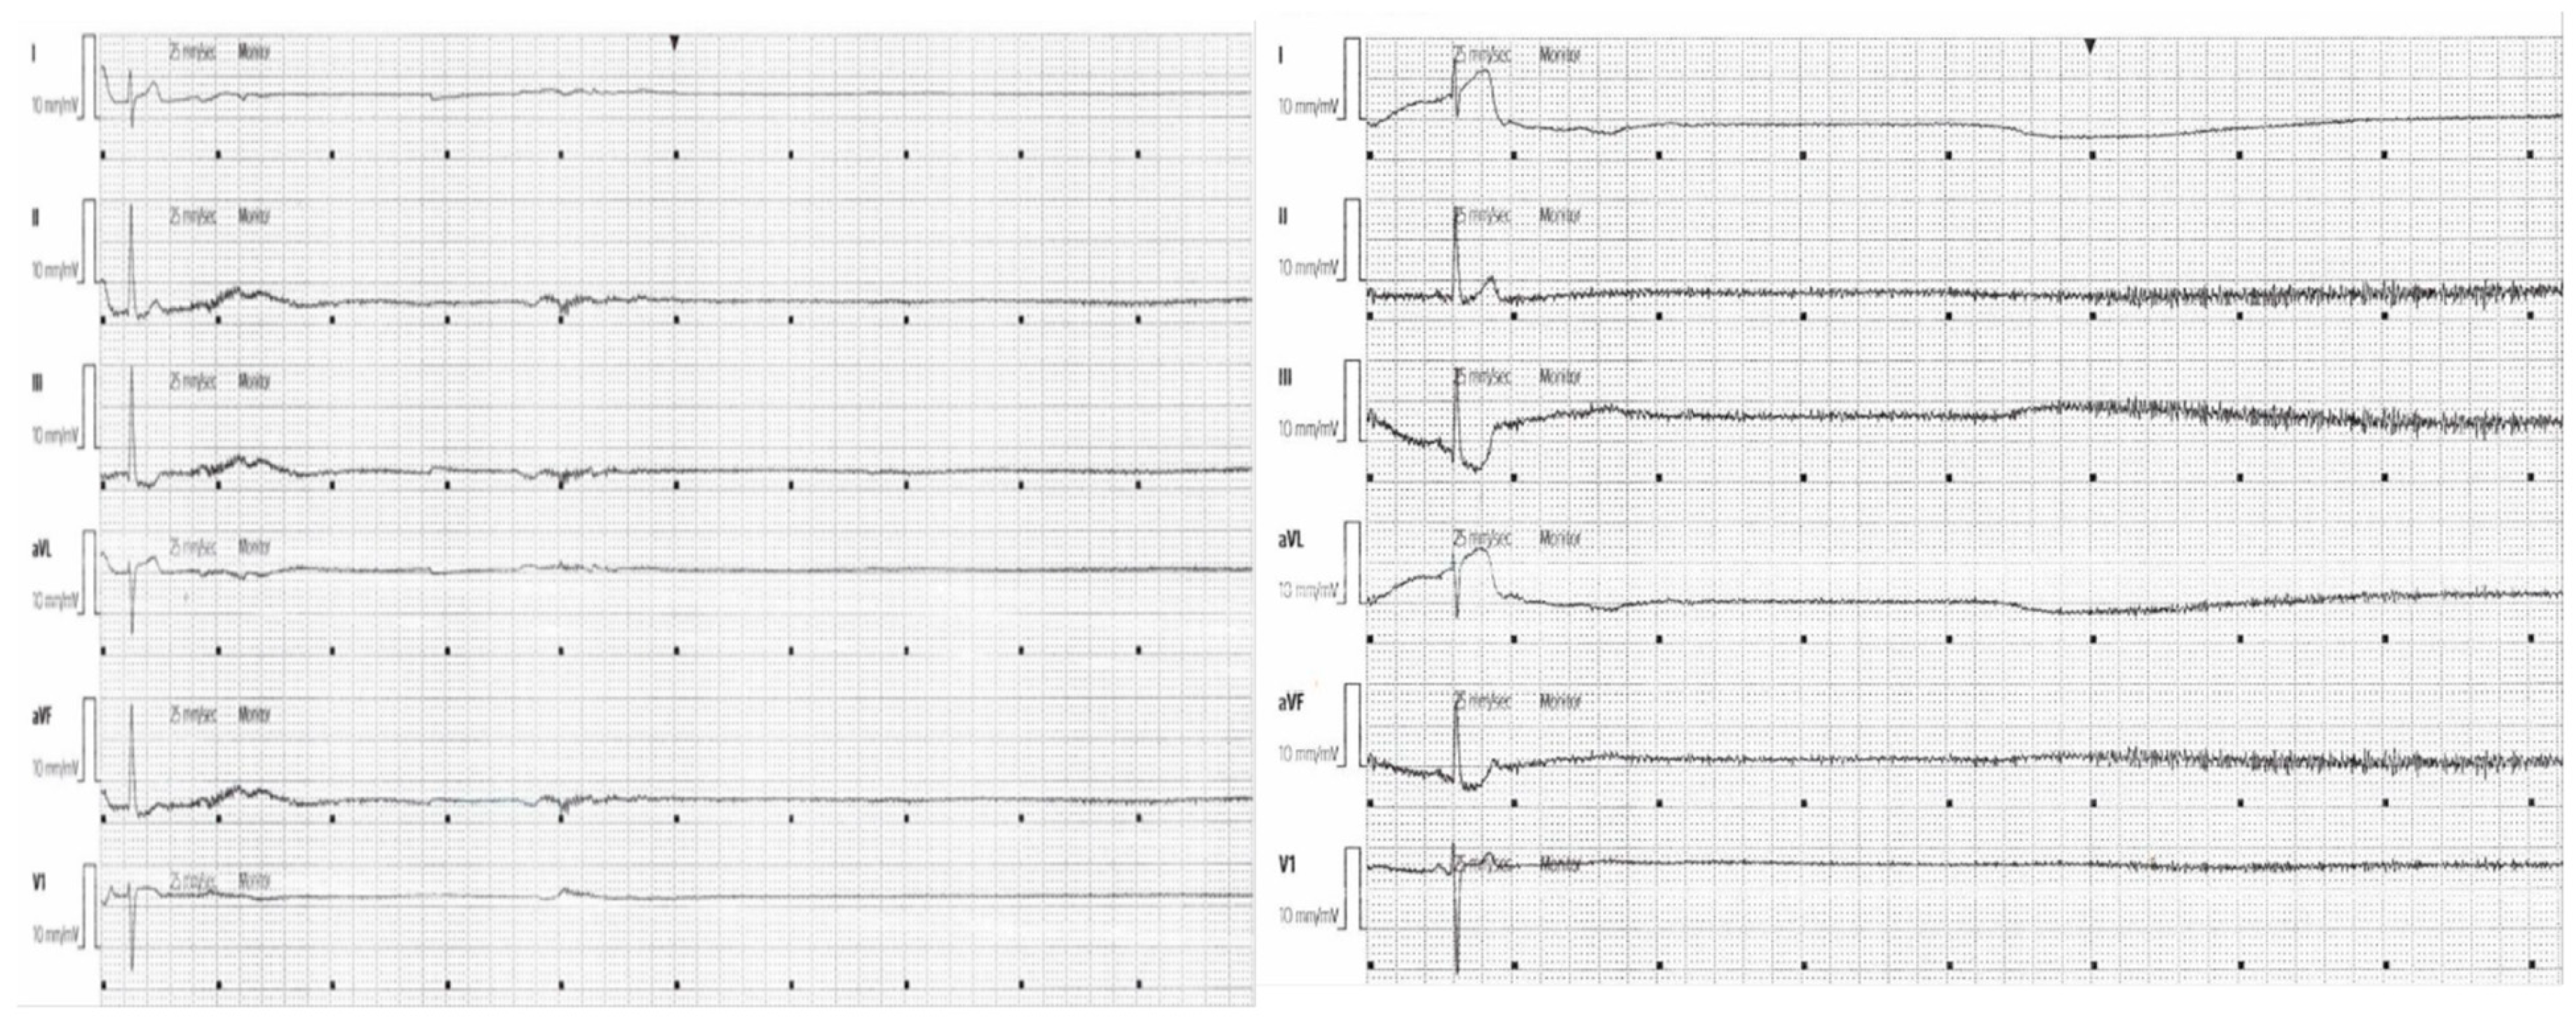

Postoperatively, the patient was admitted to the ICU. Initial ICP remained elevated at 22–25 mmHg. Sedation consisted of propofol 30–50 mcg/kg/min and fentanyl 25–75 mcg/h, and norepinephrine was titrated to maintain adequate cerebral perfusion. Approximately 12 h later, he developed multiple episodes of spontaneous sinus arrests lasting up to 15 s (Figure 2). During these events, his heart rate dropped to zero, his arterial tracing flattened, and his ICP remained within the 22–25 mmHg range, suggesting a pressure-driven autonomic disturbance. Blood pressure transiently decreased to 70/40 mmHg but recovered spontaneously. No metabolic abnormalities, hypoxia, or drug-related triggers were identified.

Figure 2. Two cardiac telemetry strips showing sinus arrests greater than 15 s each.